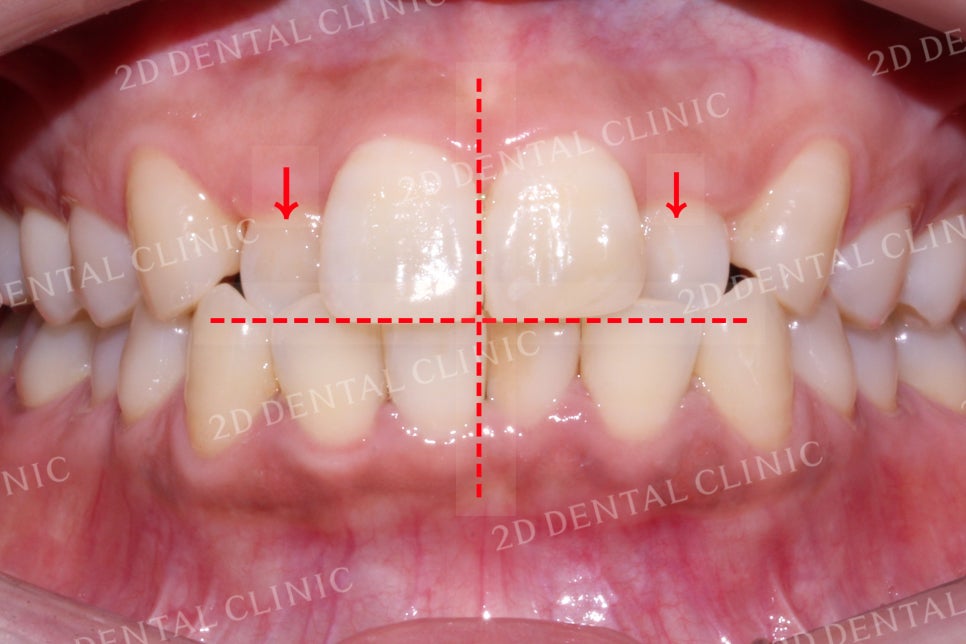

미소 시 전치부의 사진입니다.

상악의 치아들을 살펴보면

좌우의 측절치가 하악의

뒤쪽으로 물리고 있는데요,

정상적인 교합은 상악 전치부가

하악의 전치부를 살짝 덮는 정도로

물리는 것이 특징입니다.

그러나 이번 Case처럼

상하악의 치아가 거꾸로 교합된다면

'반대교합'에 해당한다고 볼 수 있습니다.